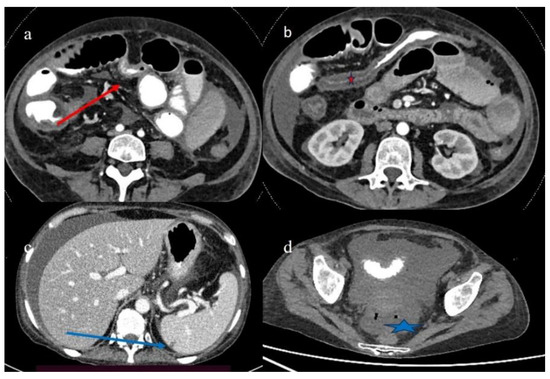

| 1 | P | P | Multisegmental and plurifocal parietal thickness with homogeneous mucosal enhancement on distal ileus | Multisegmental thickness with homogeneous mucosal enhancement | Mild diffuse comb sign and poor reactive mesenteric lymph node | Splenic infarct |

| 2 | P | P | Diffuse parietal thickness with stratified enhancement | Multisegmental thickness with homogeneous mucosal enhancement | Diffuse comb sign and poor reactive mesenteric lymph node | Mild gallbladder thickness and mild biliary tract dilatation |